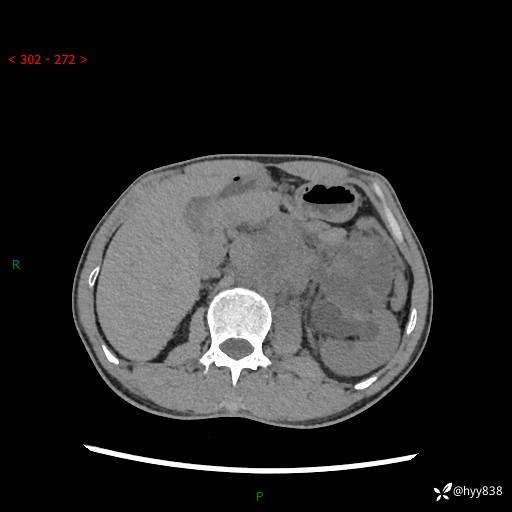

简要病史:患者无明显诱因出现左侧下腹及左侧腰背部疼痛,为间歇性隐痛,我院行胃肠镜检查,提示慢性非萎缩性胃炎,予以口服药物治疗,效果欠佳,后仍觉腹痛不适,遂至当地中医医院就诊,行彩超提示左肾积水及左肾实质性占位,遂来我院泌尿外科就诊

腹部CT平扫+增强